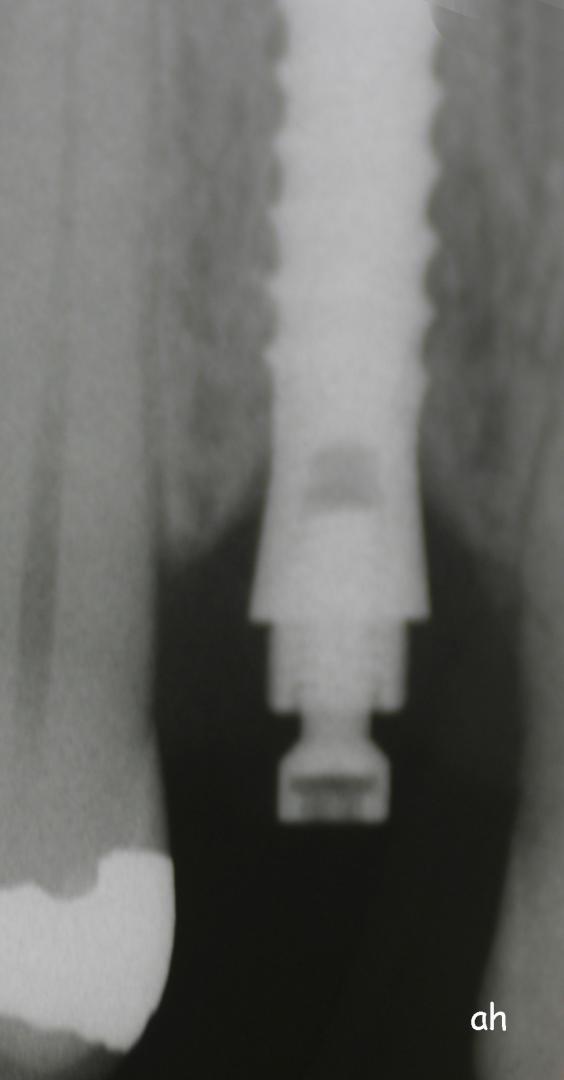

Exemple 14: Il est prévu de mettre un implant entre la molaire et prémolaire, mais le sinus se trouve à moins de 4 mm de la surface. Il faut donc relever le sinus avec une greffe d'os

Exemple 14: Un petit puits d'accès est créé afin d'atteindre le sinus, notez la membrane sinusienne.

Exemple 14: La fine membrane sinusienne est relevée, puis de l'os mélangé à de l'os artificiel est introduit dans la cavité.

Exemple 14: La cavité est maintenant remplie.

Exemple 14: Radiographie post chirurgicale.

Exemple 14: 6 mois plus tard, l'implant est introduit dans cette greffe sans toucher le sinus.